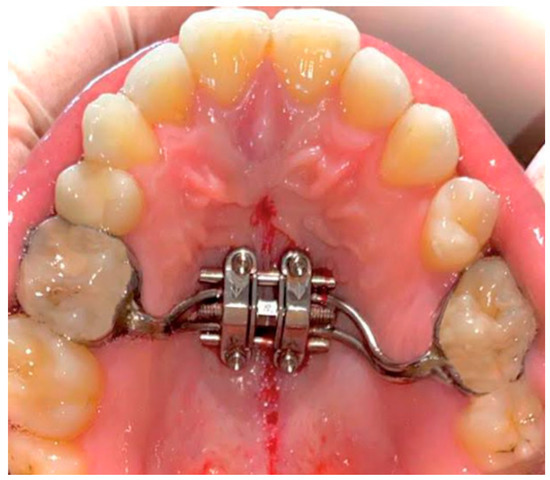

Surgical Protocol

- Suzuki, S.S.; Braga, L.F.S.; Fujii, D.N.; Moon, W.; Suzuki, H. Corticopuncture Facilitated Microimplant-Assisted Rapid Palatal Expansion. Case Rep. Dent. 2018, 2018, 1–12. [Google Scholar] [CrossRef]